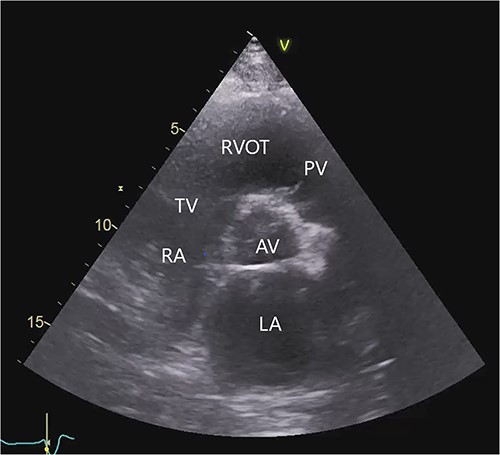

On the second postoperative day the patient showed hemodynamic impairment with signs of right ventricular failure. A temporary percutaneous RVAD was implanted with two cannulas via the right internal jugular vein (IJV) and the right femoral vein (FV). Despite RV support, LVAD flow did not increase and hemodynamic instability failed to improve. Transthoracic echocardiography revealed severe pulmonary insufficiency caused by the cannula of the RVAD. The blood recirculated in the congested right ventricle (Fig. 2, Videos S2 and S3 in the Supplementary Material online).

Transthoracic echocardiogram after implantation of a percutaneous RVAD with two cannulas via the right IJV and right FV. Parasternal long-axis view demonstrating the cannula position in the pulmonary valve (A). Color Doppler transthoracic echocardiogram after implantation of a percutaneous RVAD with two cannulas via the right IJV and right FV. Parasternal long-axis view demonstrating severe pulmonary regurgitation due to cannula position in the pulmonary valve (B). AV (aortic valve), PV (pulmonary valve), RVOT (right ventricular outflow tract), TV (tricuspid valve), * tip of cannula.